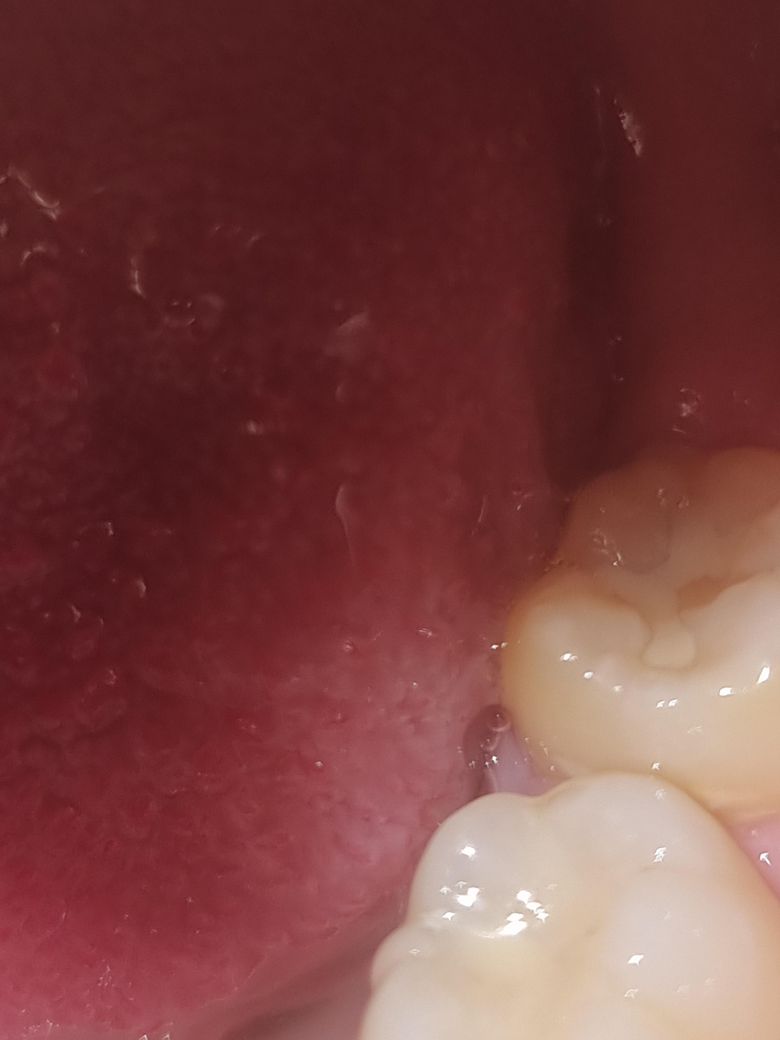

어금니쪽에 레진이 깨진건지, 아닌건지, 궁금합니다. 빨리 알려주시면, 정말 감사하겠습니다. 부탁드립니다.......

사진이 명확하지 않지만 단순히 마모가 된 것이 아닐까 의심됩니다.

사진으로는 정확한 판단이 어려워 보입니다 하지만 협죽으로 해서 충전 물에 미세한 금이 간 것이 확인이 되고 있긴 합니다 정확한 확인을 위해서는 치아가 잘 건조된 상태에서 확인을 해 보는 것이 좋을 것으로 생각됩니다

안녕하세요 치과의사 김철진입니다. 치료한 부위가 살짝 떨어져 나간거 같습니다. 치과에 가셔서 검진을 받아보시는게 좋을것같습니다.